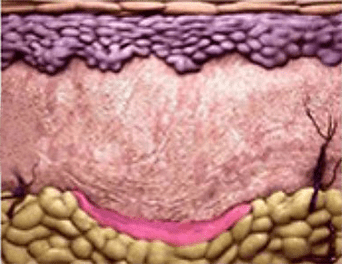

PLA 성분이 분해 되면서

콜라겐 등의

신생조직 생성을 촉진 -

약 6주 후 부터

피부복원 효과 확인 가능

자연스러운 볼륨

자가 콜라겐 재생 촉진으로

시간이 지날수록

자연스러운 효과 -